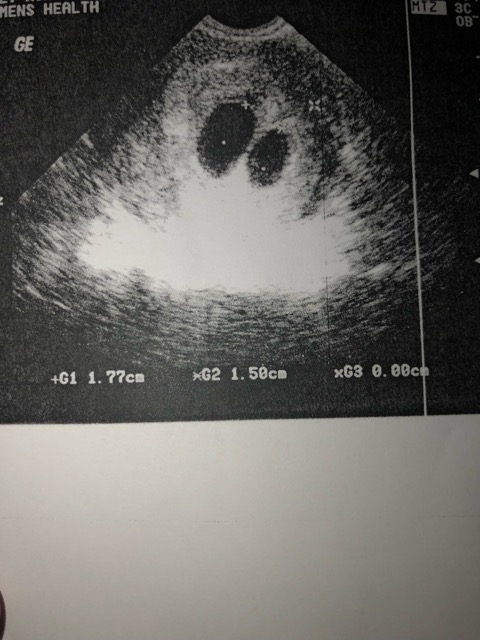

Hello everyone, I am currently 7weeks 4 days according to the first day of my lmp. I got an ultrasound done today at the local pregnancy clinic and was told I am expecting twins but there were just 2 gestational sacs with no yolk sacs/fetal poles inside. I was also told I need to return next week for follow up ultrasound to see if they are developing properly or if I need to schedule a d&c. I am completely devastated and have read in other forums that sometimes ovulation can have occurred later than expected which causes one to be earlier in pregnancy than they thought? Can this be? And has anybody experienced this?:( also the ultrasound tech mentioned she could have possibly seen something in one of the sacs. Any advice would be greatly appreciated